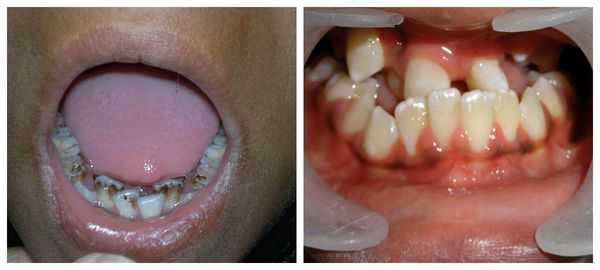

Перечисленные лицевые аномалии могут сопровождаться нарушением слуха, неправильной закладкой и прорезыванием зубов и другими нарушениями, которые могут повлиять на психофизическое развитие ребёнка.

- расщелина нёба и/или верхней губы (заячья губа).

В целом расщелины лица и/или нёба, недоразвитие верхней и нижней челюсти, лицевых мышц, скуловой и/или височной костей способны вызывать проблемы с зубами, трудности при кормлении, нарушение речи и изменение эстетических параметров лица.

Врожденная расщелина неба

Врожденная расщелина неба — не такое уж и редкое явление, она встречается примерно у 1 из 500 появившихся на свет детей. Причем, если расщепление губы обычно считается изолированным пороком, расщелина неба может как возникать сама по себе, так и быть частью какого-либо комплексного отклонения, например, последовательность Пьера Робена, синдром Кабуки, синдром Дауна и другие.

Существует очень много форм данного порока: расщелина мягкого неба, расщелина твердого неба, сквозная расщелина, затрагивающая все небо, а также скрытая расщелина, обнаружить которую удается далеко не сразу. В некоторых случаях родители, обеспокоенные плохим развитием ребёнка, медленным набором веса у малыша, грешат на недостаток молока у матери или на качество молочной смеси, пытаются найти тот самый волшебный продукт, который наконец-то поможет ребёнку насытиться, и лишь только рентгеновский снимок позволяет выявить скрытую расщелину, мешающему нормальному сосанию груди или соски.